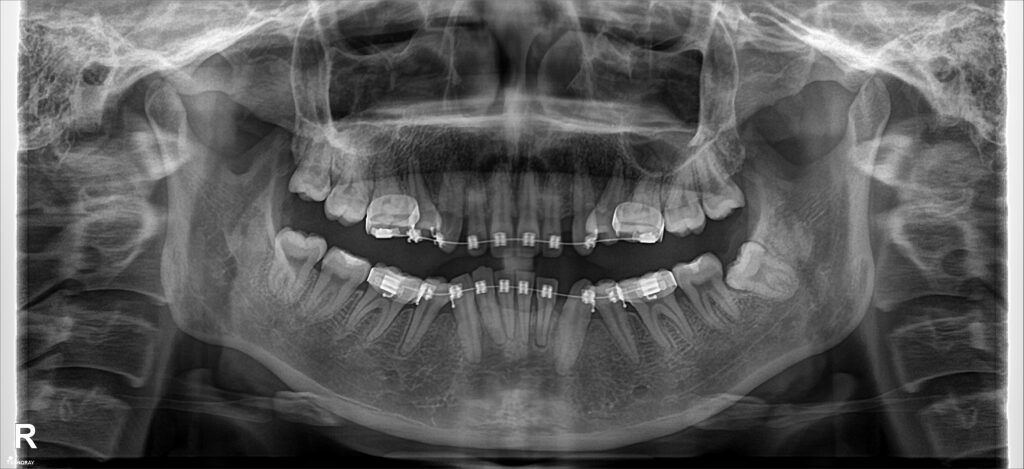

Kết quả phân tích phim: khớp cắn hạng II cả răng và xương, khớp cắn sâu 100%

Tình trạng trục răng lệch, sai nhiều do hiệu ứng cuộn & do gắn mắc cài sai.